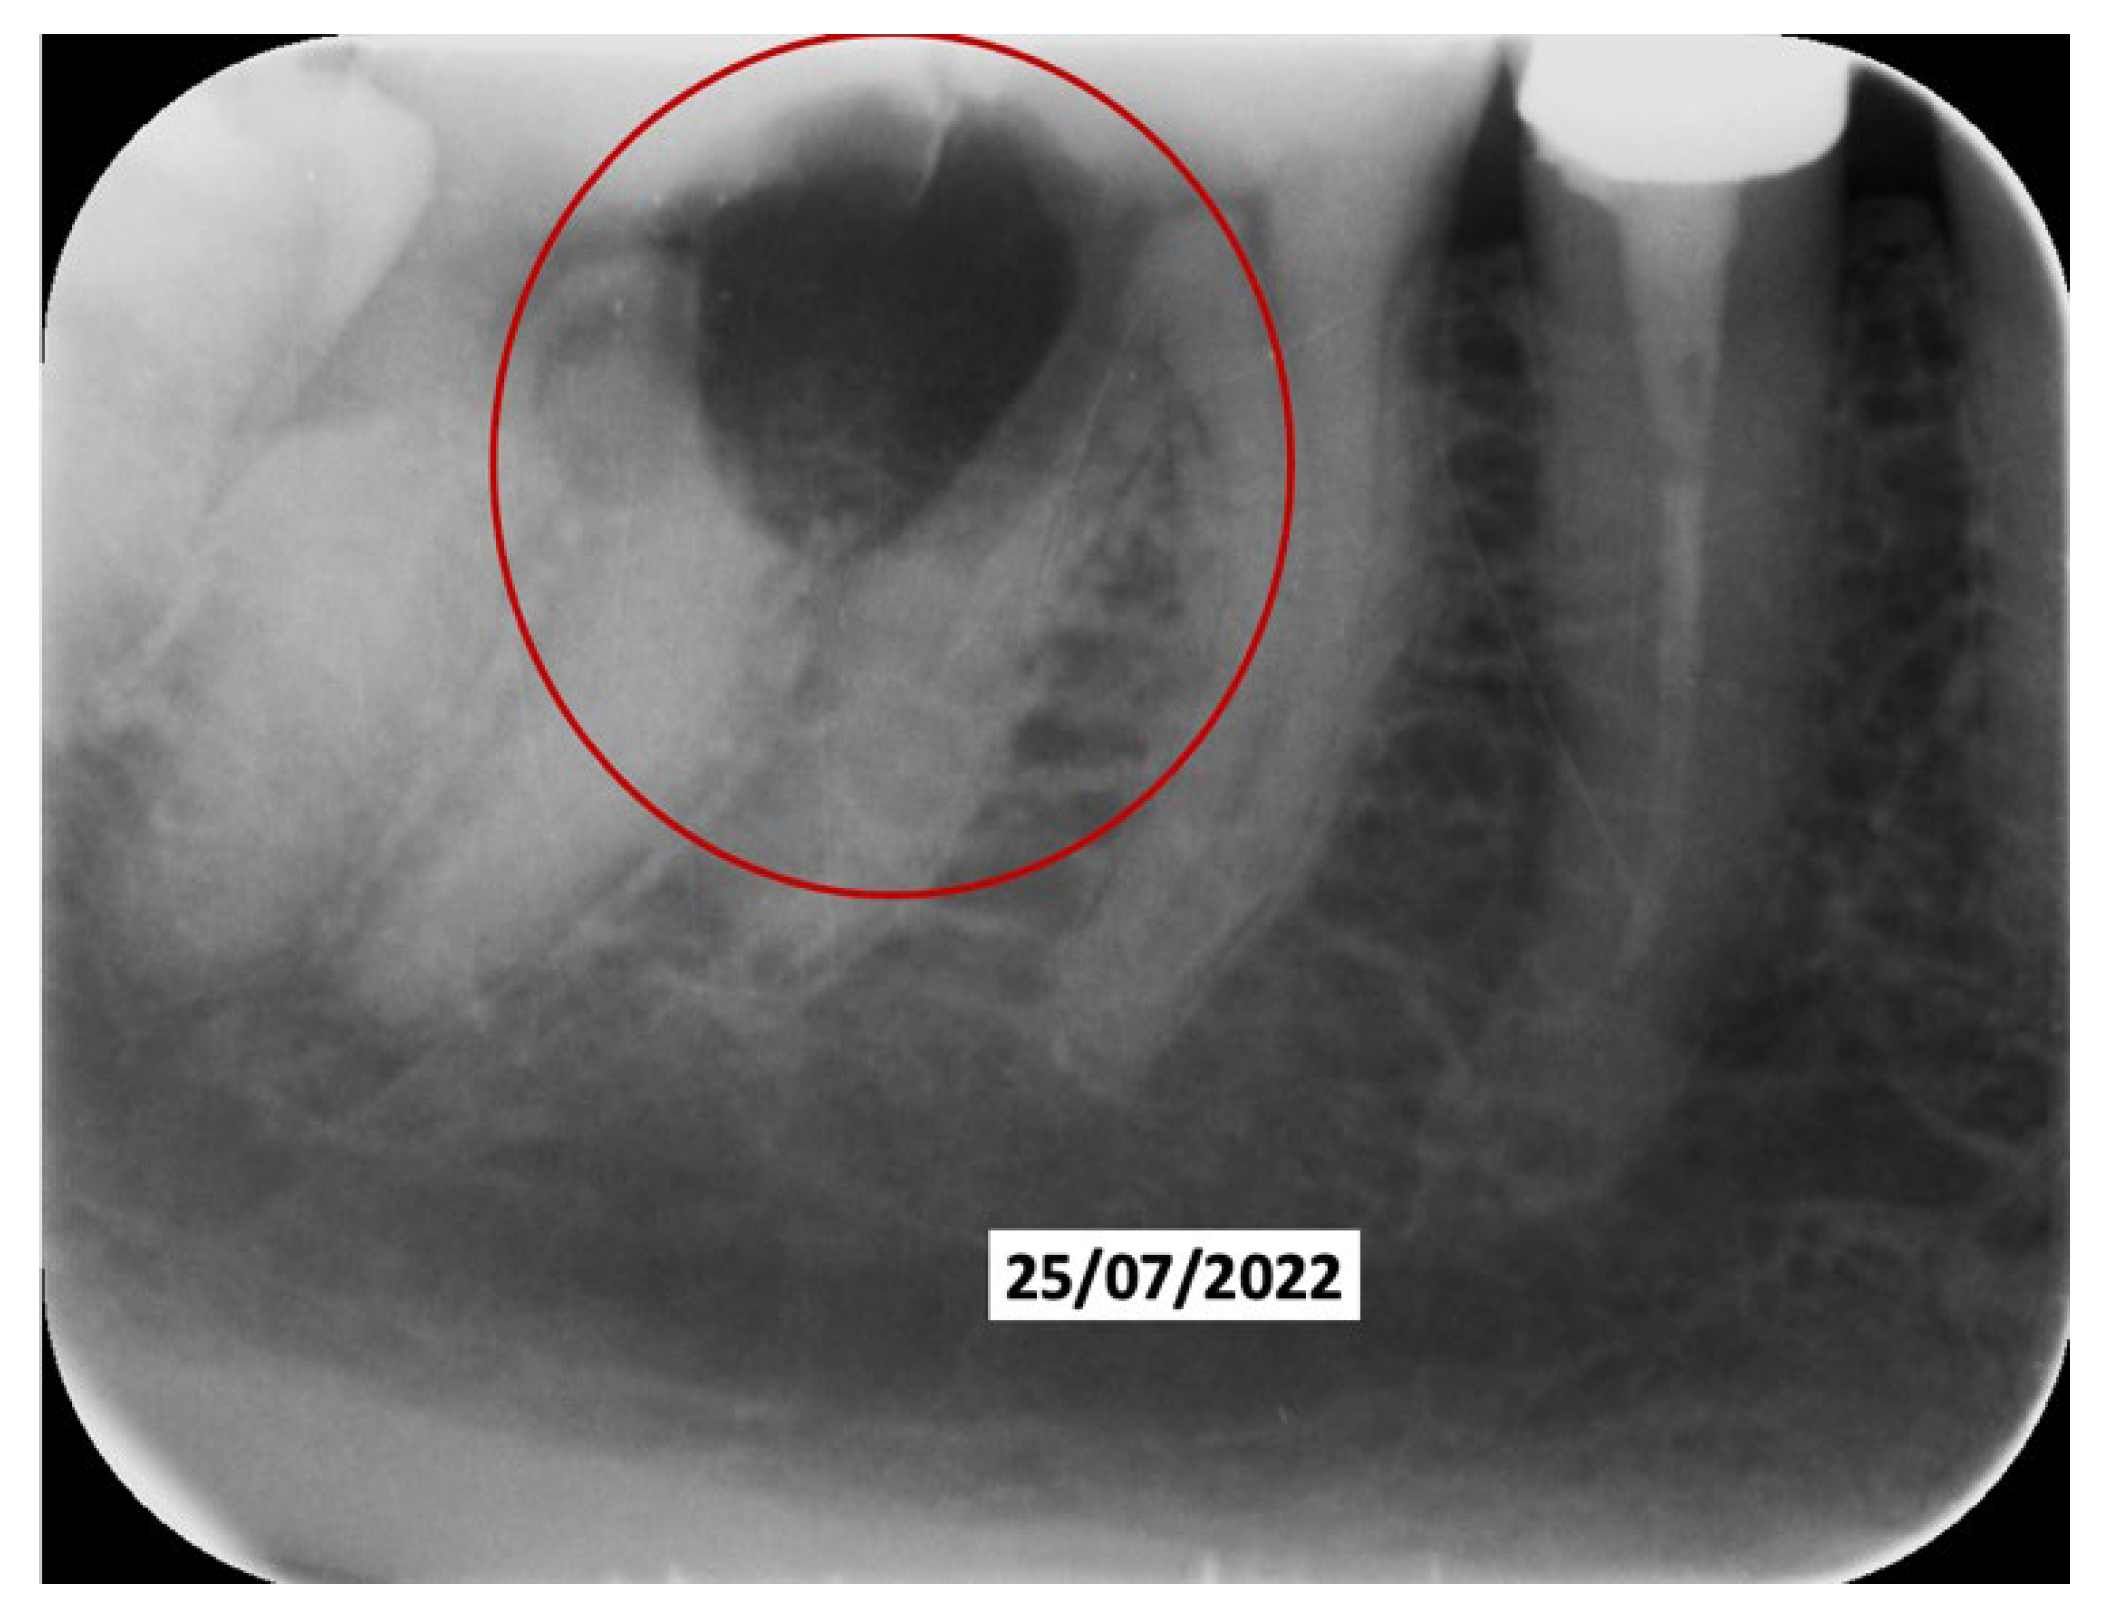

60 days after the extraction of the upper front teeth, it was discovered that the upper right premolars were also affected by significant root resorption, as well as 46 and 47 (Figure 6).

Figure 6. Evolution of the external resorptions in 46-47.